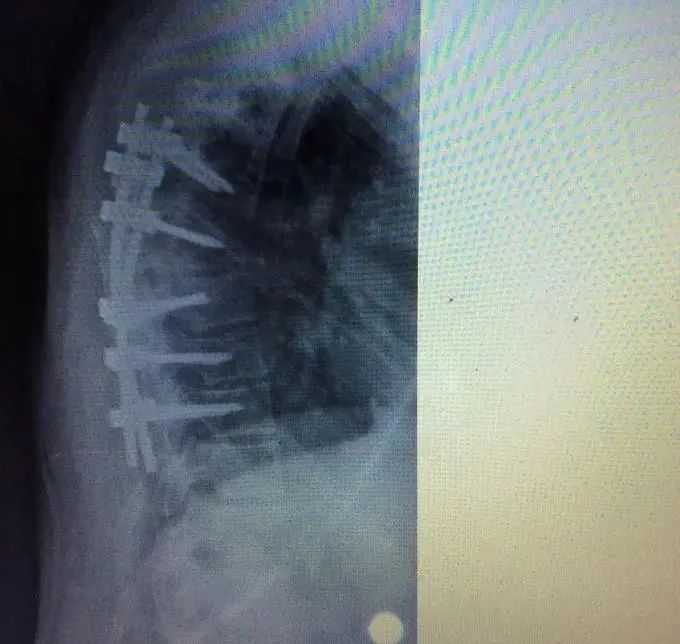

胸椎结核是因为结核菌侵蚀胸椎椎体造成的骨质破坏以及化脓性病变,一般患者会有全身症状。胸椎结核还是一种慢性骨科疾病,会侵蚀骨质和软组织,破坏骨质,并造成软组织的增生。背部痛是胸椎结核最常见的症状,疼痛的性质多为钝痛或酸痛,并且还伴有压痛及叩击痛。胸椎结核的具体症状表现有:疼痛、脊柱活动受限、肿胀、功能障碍、畸形等。

胸椎结核和其他脊柱结核一样易发于椎体,以破坏脊柱的前柱、中柱为主。而且,又因其本身存在的生理性后凸,应力集中在椎体的前侧, 患者负重后容易造成椎体塌陷,从而就导致后凸畸形十分的明显。结核杆菌喜欢生长在血液丰富的地方,人的脊椎椎体以松质骨为主。它的滋养动脉为终末动脉,静脉血流到这里速度缓慢,结核杆菌容易停留在椎体部位。于是,胸椎结核在各方面因素的影响下就产生了。 本期专家推荐